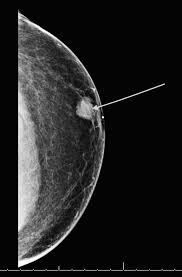

Breast cancer usually occurs in men over 60, but can very occasionally affect younger men. While breast cancer is often considered a women's disease, men can develop the condition too. Mammograms have a black background with white and gray coloring to show breast tissue. The difference between dcis and. What is ductal carcinoma in situ?

What does breast cancer feel like? What does breast cancer look like? What does breast cancer look like on mammograms? Look at the pictures and answer the following questions: What do breast lumps feel like? Grade 2 cancer cells do not look like normal cells. What is ductal carcinoma in situ? Breast cancer in men usually starts in a duct. Inflammatory breast cancer symptoms include: What breast cancer looks like in men. Advances in screening and treatment for breast cancer have improved survival rates dramatically. We do get men ringing us asking questions about their breast health, so we're always there for anyone who wants to ask questions and talk through concerns, she. Male breast cancer is rare and affects 2.7 out of 100,000 african american men and 1.9 out of 100,000 caucasian men in the united states.

About Our Program For Breast Cancer In Men Dana Farber Cancer Institute Boston Ma from www.dana-farber.org Care guide for breast cancer in men. Male breast cancer is rare and affects 2.7 out of 100,000 african american men and 1.9 out of 100,000 caucasian men in the united states. What does breast cancer look like on a mammogram? My experience of having breast cancer will shape my future career. Male breast cancer does occur and it looks on a mammogram the same as female. It often presents as a new lump or mass in the breast/chest. What does a breast cancer lump feel like? The risk of a man getting the major problem is that breast cancer in men is often diagnosed later than breast cancer in women.

What does breast cancer look like on mammograms? As the tumor grows, a person may be able to feel a lump. Experts say breast cancer can affect men of any age, but it's most common in older men. Noticing an unusual change doesn't necessarily mean you have breast cancer, and most breast changes are not because of men can also develop breast cancer but it is very rare. What is invasive breast cancer versus noninvasive breast cancer? Learn about breast cancer symptoms and signs and what to do if you're worried about a change in your breasts. If there is a scratch on your knee put iodine on it. What does breast cancer feel like? However, breast lumps are common, and not all of them are cancerous. Having one papilloma does not raise your breast cancer risk, though having several of these growths. But other than looking out for symptoms, what's another sure way to test for a cancerous lump? The prognosis for breast cancer in men is similar to the prognosis in women at the same stage of diagnosis. Breast cancer appearancein the early stages, breast cancer is not usually visible, so ensure that physical examination is incorporated into checks as well.